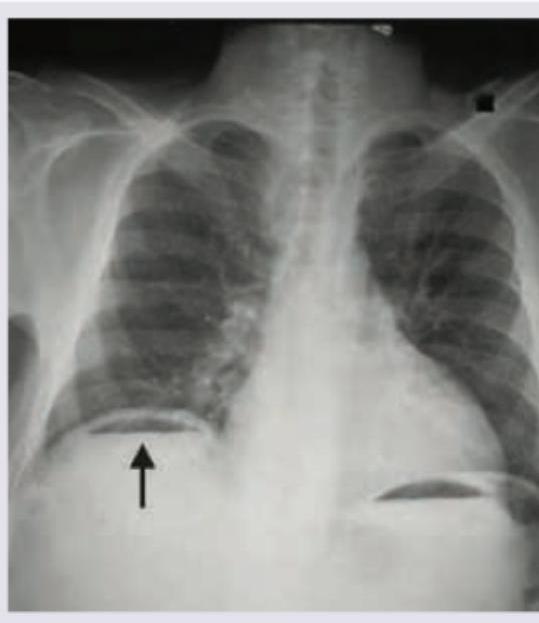

Question 1: What does the given chest X-ray show?

- A. Pneumoperitoneum (Correct Answer)

Explanation: ***Pneumoperitoneum*** - The chest X-ray shows **free air under the diaphragm**, visible as a lucent (dark) crescent between the liver/spleen and the diaphragm (indicated by the arrow on the right side of the patient). - This finding is diagnostic of **pneumoperitoneum**, which is often caused by a perforated abdominal viscus like a peptic ulcer or bowel perforation. *Emphysema* - **Emphysema** is a lung condition characterized by over-inflated alveoli and air trapping within the lungs, leading to hyperlucency of the lung fields and flattened diaphragms. - It does not present as free air below the diaphragm but rather as changes within the lung parenchyma. *Diaphragmatic hernia* - A **diaphragmatic hernia** involves the protrusion of abdominal organs into the chest cavity through a defect in the diaphragm. - This would typically show abdominal contents (e.g., bowel loops or stomach) above the diaphragm in the thoracic cavity, not free air below it. *Diaphragmatic eventration* - **Diaphragmatic eventration** is an abnormal elevation of part or all of an intact hemidiaphragm due to thinning and weakness of the diaphragmatic muscle. - It causes an elevated diaphragm but does not involve free air in the peritoneal cavity.